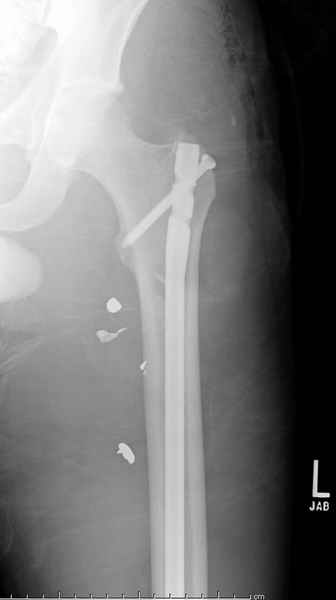

Входные маленькие отверстия от ранении просто игнорируются, никаких дренажей, как любое колотое ранения, они закрываются и были случаи через месяц. Конечно, ведется профилактика открытых ранении: сыворотки и т.д., но еще самое главное уделяем профилактике образования перелома из-за стресса в результате дефекта кортикального слоя.

Литературные данные о влиянии кортикального дефекта на стрессовые переломы в длинных трубчатых костях в основном встречаются в онкологии, например кортикальный дефект более 50% имеет больше шанса стрессовых переломов, чем в нашем случае.

Учитывая, что больной получил травму не во время визита в церковь, и он является одним из представителем 40 миллионного “outstanding itizen”, без медицинской страховки, без работы в свои 39 лет, и без надлежающей ортопедической дисциплины у которого отсутсвует страх стрессового перелома, было рекомендовано оперативное лечение: профилактическое антеградное интрамедуллярное штифтование.